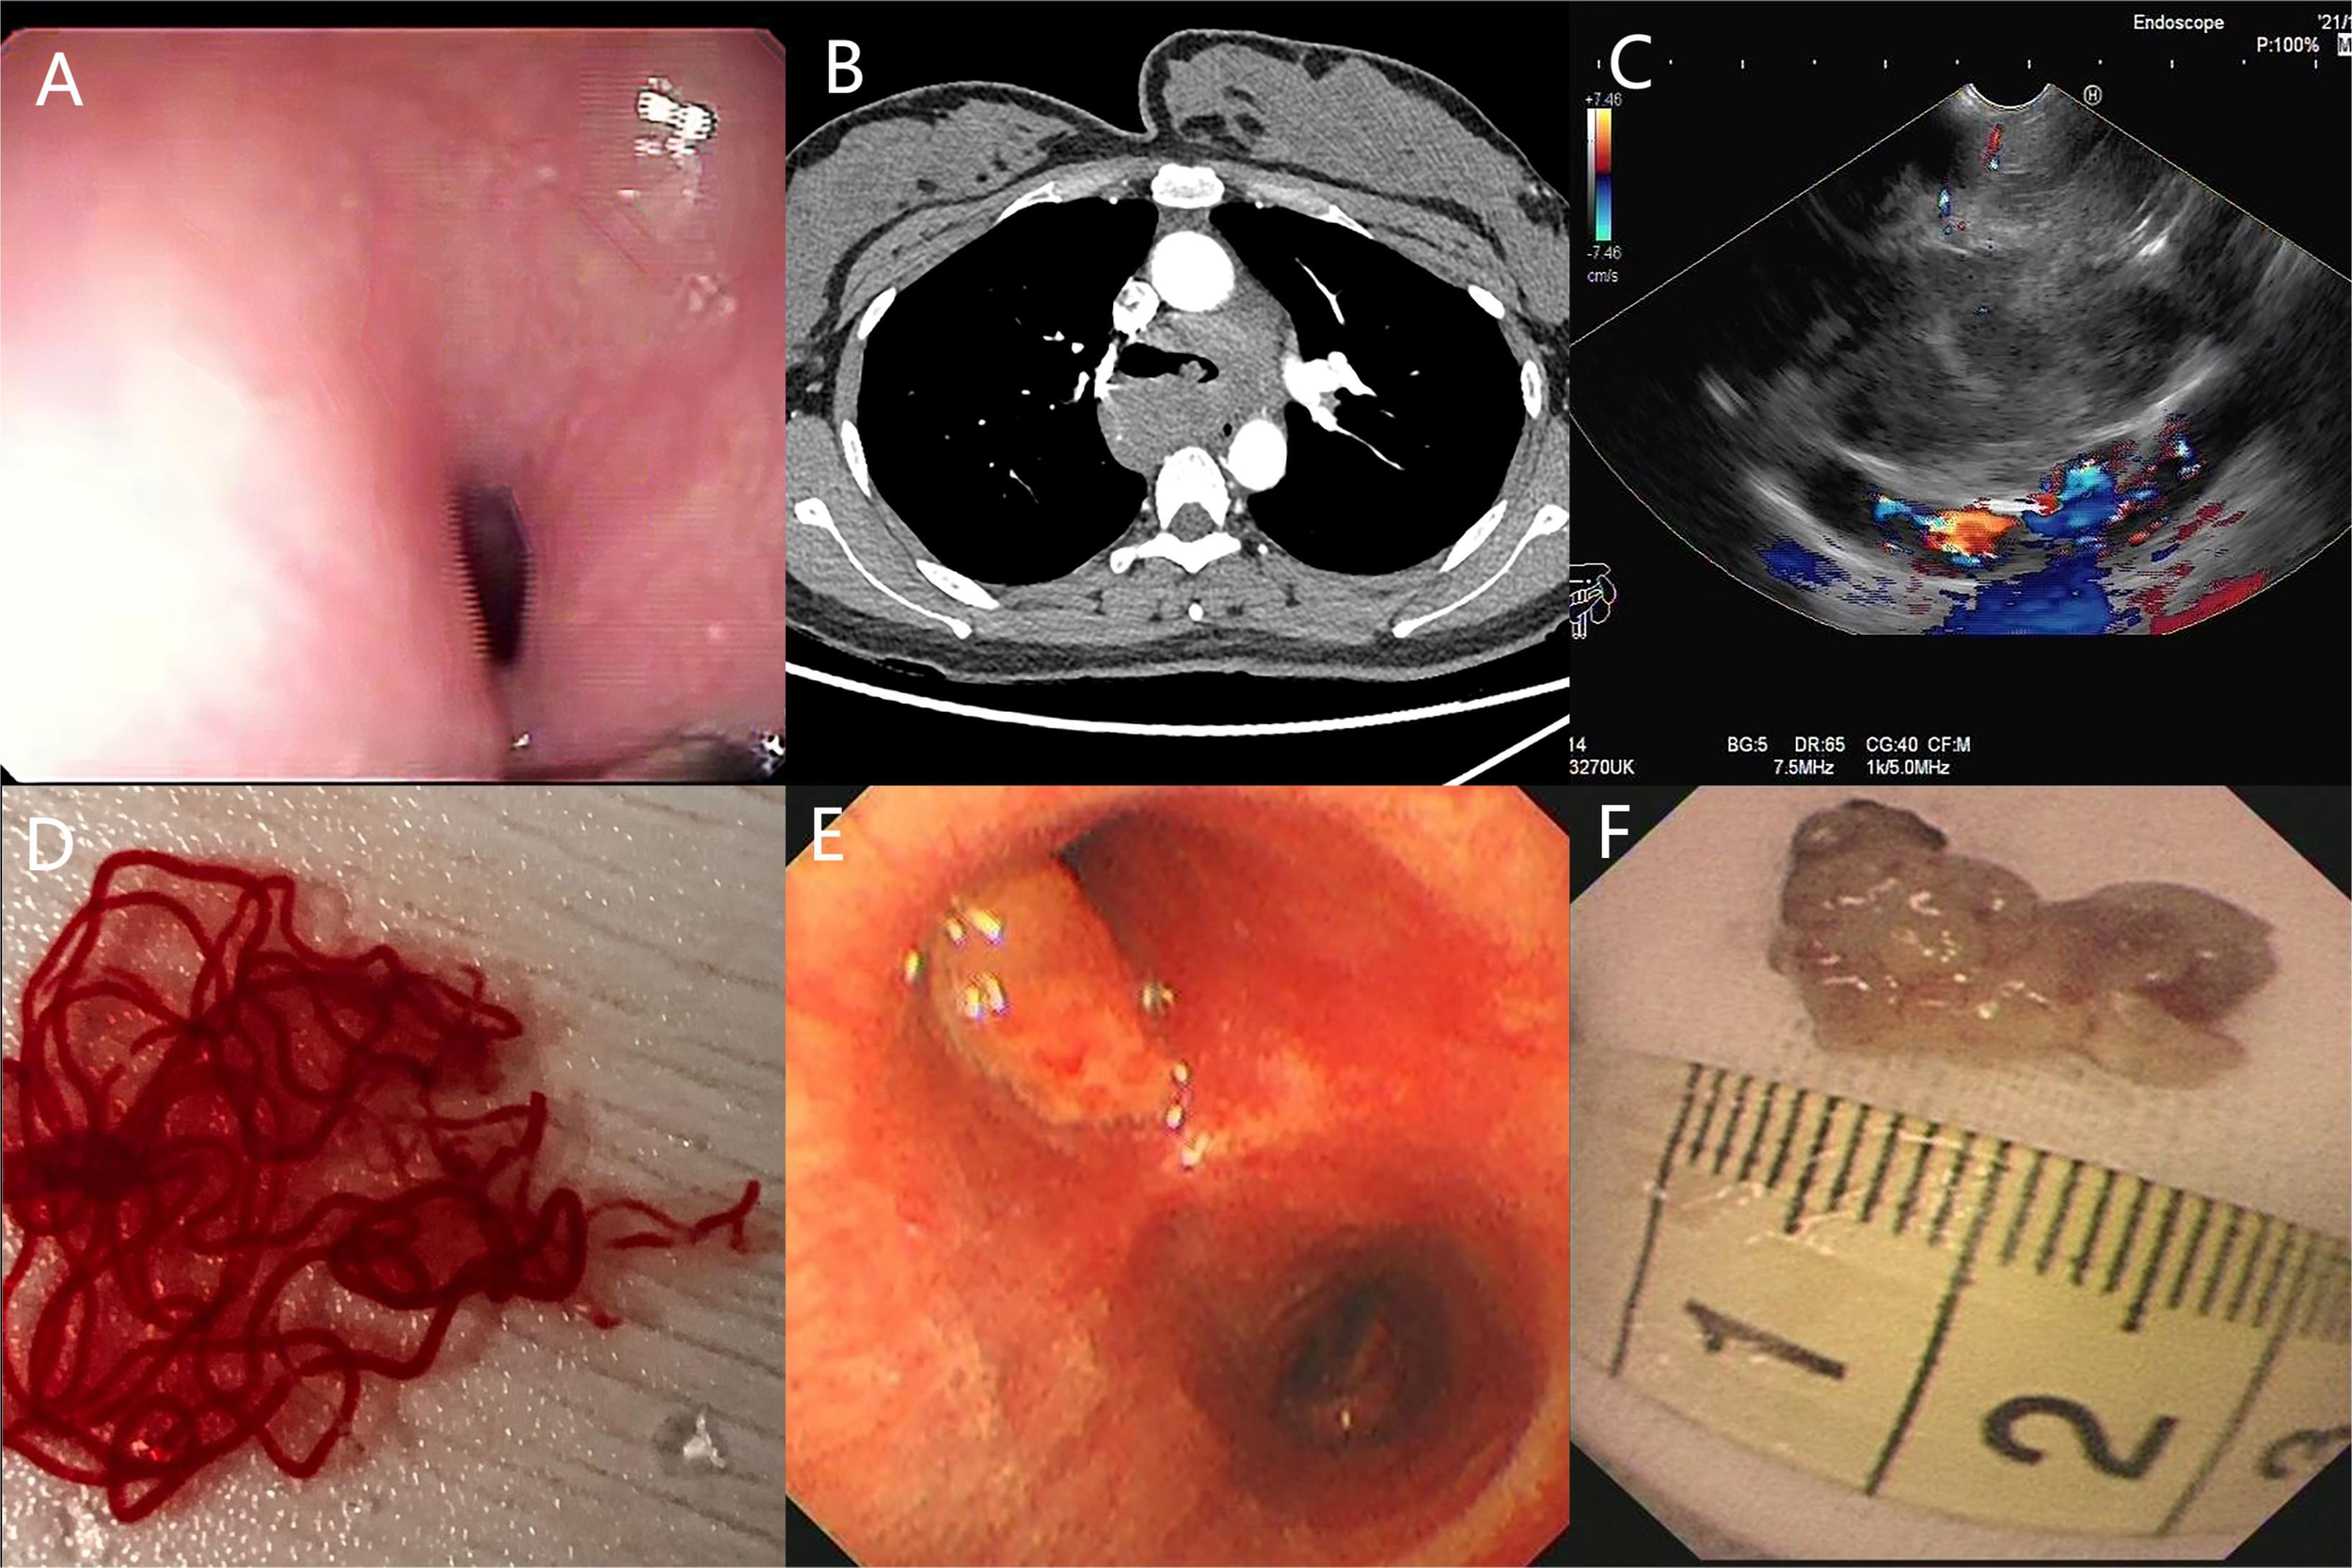

The patient underwent a series of diagnostic assessments. Initial gastroscopy revealed a significant submucosal bulge in the middle segment of the esophagus (Figure 1A). Then, a contrast-enhanced computed tomography scan of the chest showed a left main bronchus nodule measuring 15 mm, mediastinal lymph node enlargement, and fusion with necrosis (Figure 1B). Subsequently, we obtained the tissue from the mediastinal mass through EUS-FNA (Figures 1C, D) and the tissue from the left main bronchus nodule through transbronchoscope biopsy (Figures 1E, F). Both of the samples’ pathological results revealed a large number of tumor cells proliferating diffusely. The tumor cells were medium to large, and the cytoplasm was rich and transparent. The nucleus was round or oval, and the nuclear chromatin consisted of coarse particles or vacuoles. Tumor cells were often divided into nests by proliferating fibrous cords (Figure 2). Based on clinical evidence, the patient was considered to have a lymphoma. Due to the complexity of lymphoma classification, different types of lymphoma have different treatment options, and it is very important for patients to clarify the pathological type.

Figure 1

(A) Gastroscopy shows a huge submucosal bulge in the middle of the esophagus. (B) Contrast-enhanced computed tomography scan of the chest shows a left main bronchus nodule, mediastinal lymph node enlargement, and fusion with necrosis. (C, D) Endoscopic ultrasound reveals a 30 × 25-mm hypoechoic lesion arising from the mediastinal mass, and EUS-FNA was performed to obtain tissue from the mass. (E, F) Transbronchoscope biopsy was performed to obtain tissue from the left main bronchus nodule.